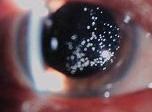

在裂隙燈下觀察,玻璃體腔內有光學空隙,附近有點狀白色渾濁或膜狀物飄浮。玻璃體液化的發生率隨年齡和眼軸長度增加。無晶狀體眼、炎症、外傷、近視、出血等,也與玻璃體液化有關。